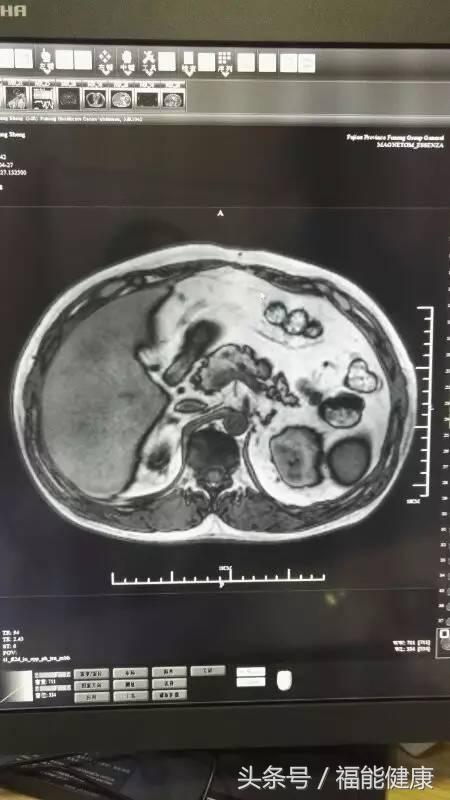

据福能健康管理中心放射影像科主任郑章和介绍,核磁共振对脑、甲状腺、肝、胆、脾、肾、胰、肾上腺、子宫、卵巢、前列腺等实质器官以及心脏和大血管以及骨关节都有很好的诊断功能。核磁共振的原理实际上是,将人体置于特殊的磁场中,用无线电射频脉冲激发人体内氢原子核,引起氢原子核共振,并吸收能量。在停止射频脉冲后,氢原子核按特定频率发出射电信号,并将吸收的能量释放出来,被体外的接受器收录,经电子计算机处理获得图像,这就是核磁共振成像的基本原理。

郑主任谈到,许多人对核磁共振检查的认识是有误区的。实际上,核磁共振是磁场成像,没有放射性,对人体无害,非常安全,这是核磁共振的优势之一。此外,核磁共振在发现病变及发现肿瘤方面也是一把好手,与其他辅助检查手段相比,核磁共振具有成像参数多、扫描速度快、组织分辨率高和图像更清晰等优点。

核磁共振检查不仅可以早期发现某些肿瘤、脑梗塞、脑出血、脑脓肿、脑囊虫症及先天性脑血管畸形,还能确定脑积水的种类及原因等。通过对头部及心脏等部位的核磁检查,在身体健康尚未发出红灯警讯前,早期发现心脏病、脑梗等高风险疾病隐患。当然,MR检查也不是万能的,在很多情况下也需要结合DR、超声、CT等手段,互为补充。同时,在诊断疾病的时候,尚需要密切结合临床其他资料。